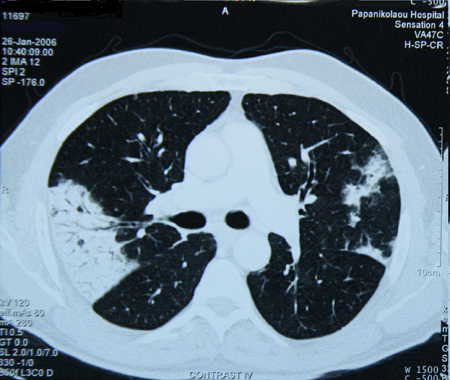

Some medications (e.g., amiodarone, bleomycin, cyclophosphamide, vincristine, taxanes), cocaine, or other illicit drug use may cause persistent pulmonary abnormalities.[18]Lynch JP 3rd, Sitrin RG. Noninfectious mimics of community acquired pneumonia. Semin Respir Infect. 1993 Mar;8(1):14-45.

Patients with malignancies undergoing chemotherapy or radiotherapy may present with persistent pulmonary infiltrate due to not only their malignancy but also complications of treatment.[26]Maschmeyer G, Carratalà J, Buchheidt D, et al. Diagnosis and antimicrobial therapy of lung infiltrates in febrile neutropenic patients (allogeneic SCT excluded): updated guidelines of the Infectious Diseases Working Party (AGIHO) of the German Society of Hematology and Medical Oncology (DGHO). Ann Oncol. 2015 Jan;26(1):21-33.

[Figure caption and citation for the preceding image starts]: Chest CT scan of a patient with amiodarone pulmonary toxicity showing asymmetric opacities with a peripheral distributionFrom the collection of Athanasia Pataka, MD [Citation ends].